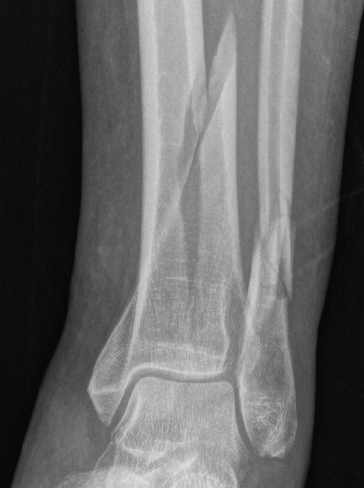

CT scan

Commonly 3 fracture configurations

- medial malleolus

- posterolateral fragment / Volkmann

- anterolateral fragment / Chaput